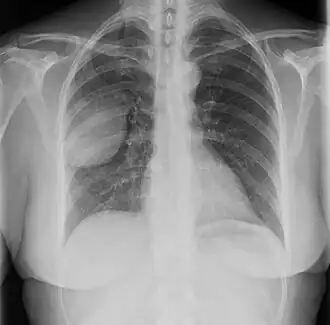

Les tumeurs fibreuses solitaires pleurales sont visualisées sur la radiographie thoracique comme des masses bien délimitées. Les clichés radiologiques standards sont cependant peu utiles pour les autres localisations[17].

Les tumeurs pleurales sont asymptomatiques dans 72 % des cas ; lorsque les signes cliniques sont présents, ils sont dominés par la toux, la dyspnée et les douleurs thoraciques[27]. Un épanchement pleural est parfois présent[28],[29] (environ 10 % des cas[30]). Les tumeurs abdominales se manifestent par des douleurs abdominales et une constipation, parfois une rétention d'urine, et sont parfois accompagnées d'une tuméfaction palpable[31].